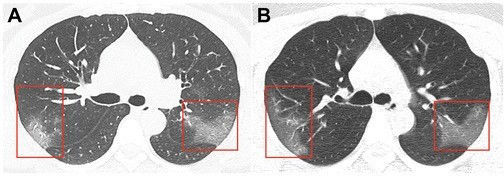

Ens.az oxu.az-a istinadən xəbər verir ki,“Radiology” jurnalında dərc edilmiş şəkillər Çinin Lançjou şəhərində 39 dərəcə temperaturla xəstəxanaya yerləşdirilmiş 33 yaşlı qadının kompüter tomoqrafiyasıdır.

Birinci şəkildə görünən "tutqun şüşə effekti” üç gün sonra çəkilmiş ikinci şəkildə daha da artır.